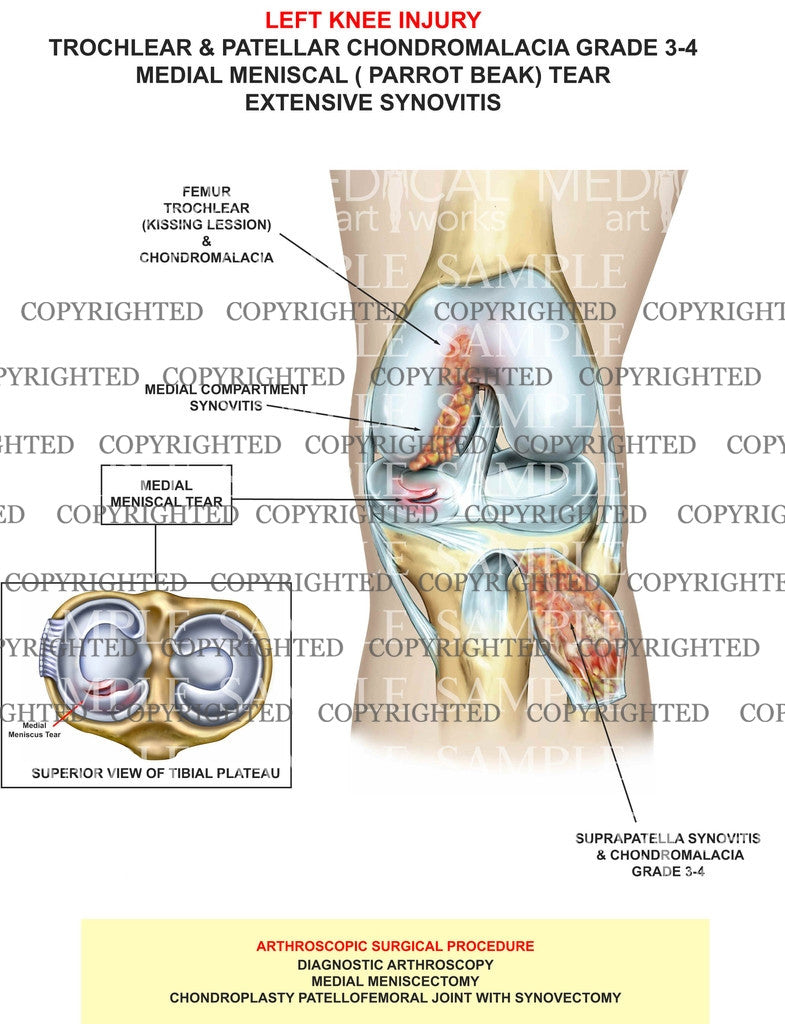

Trochlear & Patellar Chondromalacia

Trochlear & Patellar Chondromalacia

Trochlear & Patellar Chondromalacia grade 3-4

medial meniscal ( parrot beak) Tear

extensive Synovitis